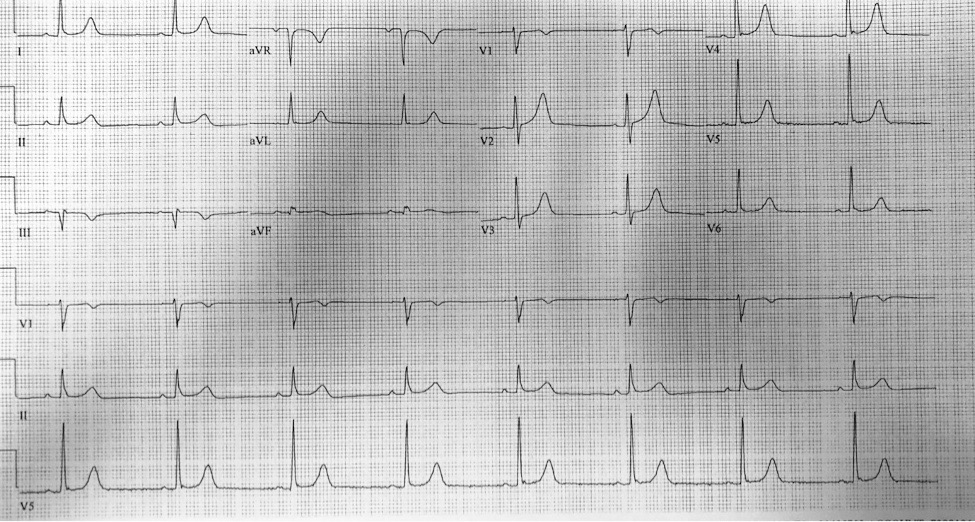

Initial EKG:

In the inferior leads there is subtle submillimeter ST segment elevation. There is starting to be the loss of a concave shape ST segment in III and aVF. There is no reciprocal change.